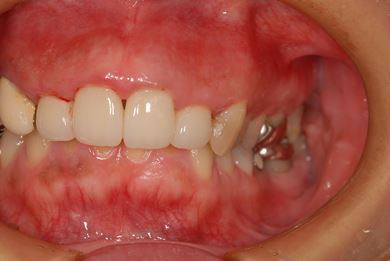

| 性別/年齢 | 女性 / 41歳 | ||||||||||||||||||||||||||||||||

| 主訴 | 歯が欠けたので、セラミック治療をお願いしたい。 | ||||||||||||||||||||||||||||||||

| 治療方針 | セラミック治療にて、審美的回復を行う。 | ||||||||||||||||||||||||||||||||

| 治療内容 | エンプレスオールセラミッククラウン4本(オールセラミック用土台4本) | ||||||||||||||||||||||||||||||||